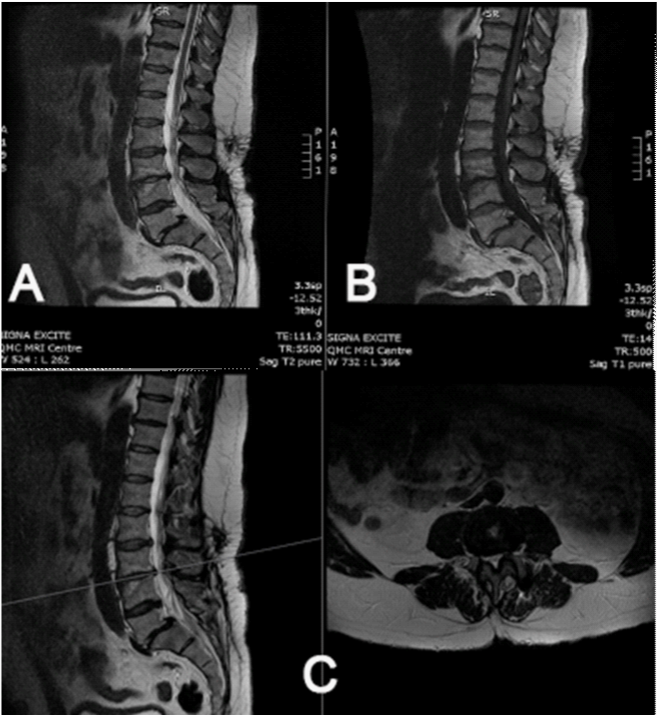

On presentation patient confessed and accepted the fact that he could never been pain free but stated on the top of his normal back and leg pain he had developed a much worse back pain just above his normal pain. He stated that the pain on his back had significantly worsened over the last 2 years as opposed to his leg symptoms that had remained unchanged. On examination, he was an obese gentleman with slightly positive saggital balance and a long posterior lumbar surgical scar. There was also an intrathecal morphine pump in his left loin. Neurological examination was unremarkable apart from knee reflexes been diminished bilaterally. Plain x-rays confirmed the presence of intrathecal catheter and implants were remaining intact and in situ and also demonstrated some evidence of L4-S1 bony fusion (Figure 1), which was further confirmed with CT scan. At L3-L4 level it demonstrated disc space narrowing and endplate sclerosis suggestive of adjacent segment disease requiring further imaging investigations. An MRI scan of the lumbasacral spine showed severe degeneration of the L3-L4 disc (adjacent level to previous fusion) with associated lateral recess stenosis impinging the left L2 and the right L3 nerve roots (Figure 2).

Figure 2 A-B) Sagittal MRI T1 and T2 sequences of the lumbosacral region showed severe degeneration of the L3-L4 disc with associated type 1 Modic changes. C) Sagittal T2 and axial T2 cuts at the level of L3-L4 demostrating lateral recess stenosis impinging the right L3 nerve root.